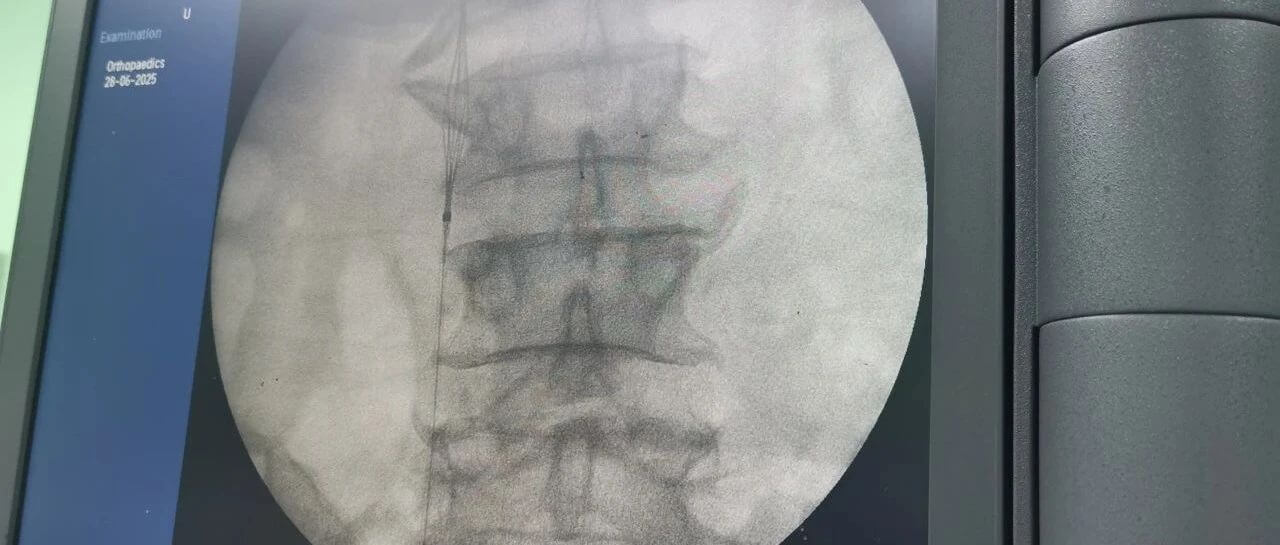

面對這一嚴峻挑戰(zhàn),羅軍副院長團隊果斷決策,先行實施“下腔靜脈濾器植入術”。手術團隊憑借精湛的技術,在患者的下腔靜脈(人體最大的靜脈干)內(nèi)精準放置了一個特殊的“濾網(wǎng)”裝置——腔靜脈濾器。它的核心作用就是充當“血栓攔截網(wǎng)”:

攔截脫落的血栓:有效捕捉從下肢深靜脈脫落的血栓碎片,防止其隨血流進入心臟和肺部。

預防致命肺栓塞:從根本上大幅降低患者在骨折手術期間及術后康復階段發(fā)生肺栓塞的風險。

保障后續(xù)手術安全:為接下來必須進行的、耗時較長的骨盆髖臼粉碎性骨折修復手術(尤其是利用3D打印技術進行的精準手術)掃除了最大的安全隱患,提供了至關重要的手術安全保障期。